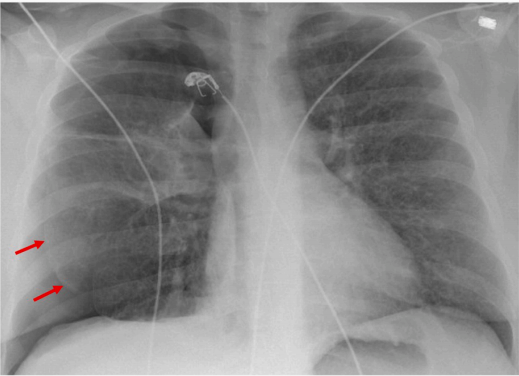

胸片显示右侧气胸,伴少量至中度积液(图1)。CT显示右侧大量气胸和同侧胸腔积液

图1 胸片显示中度右侧气胸(红色箭头)